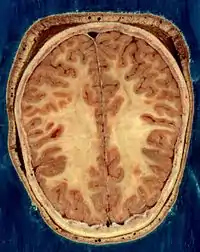

Строение головного мозга

Объём мозга большинства людей находится в пределах 1250—1600 кубических сантиметров и составляет 91—95 % ёмкости черепа. В головном мозге различают пять отделов: продолговатый мозг; задний, включающий в себя мост, мозжечок и эпифиз; средний; промежуточный; и передний мозг, представленный большими полушариями. Наряду с приведённым выше делением на отделы, весь мозг разделяют на три большие части:

- полушария большого мозга;

- мозжечок;

- ствол мозга.

Кора большого мозга покрывает два полушария головного мозга: правое и левое.

Полушария большого мозга извне покрыты серым веществом, образующим кору большого мозга, или плащ. В коре насчитывается 15 млрд клеток, а если учесть, что каждая из них имеет от 7 до 10 тыс. связей с соседними клетками, то можно сделать вывод о гибкости, устойчивости и надёжности функций коры. Поверхность коры значительно увеличивается за счет борозд и извилин. Кора филогенетическая является самой большой структурой мозга, её площадь примерно 220 тысяч мм2.